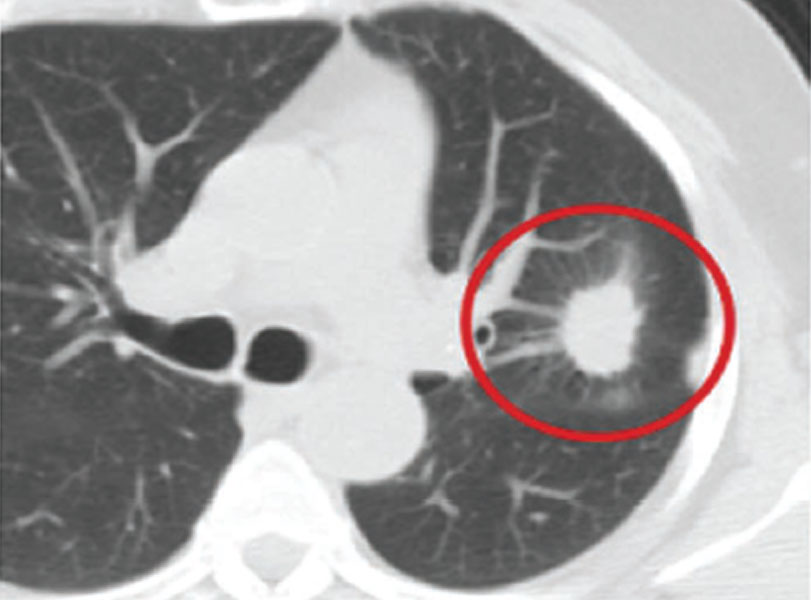

நுரையீரல் புற்றுநோய்

நுரையீரல் புற்றுநோய் எந்த வித அறிகுறிகள் இல்லாமல் உருவக கூடும், ஆகவே அறிகுறிகள் தென்படும் முன்பே CT - கெஸ்ட் (நுரையீரல்) பரிசோதனை தேவை.

CT பரிசோதனையில் நுரையீரல் புற்றுநோய் கண்டுபிடிக்கப்பட்டுள்ளது.